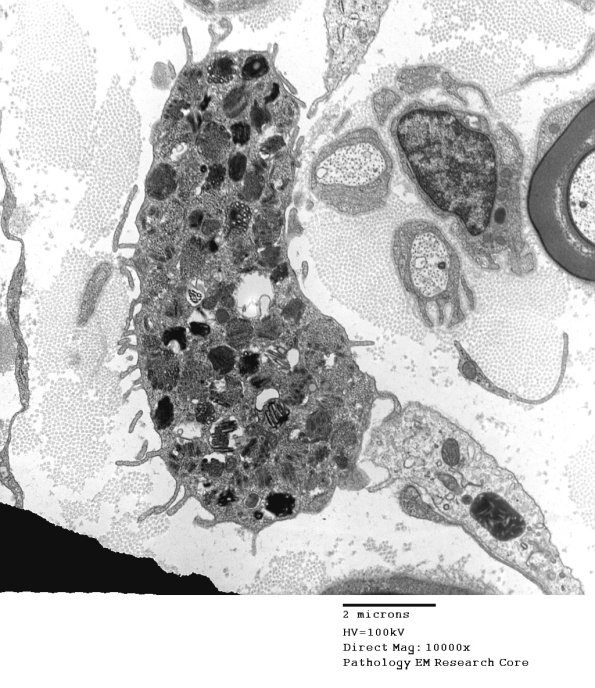

5A1-3 The same scroll pattern characterizes the granules in another case.